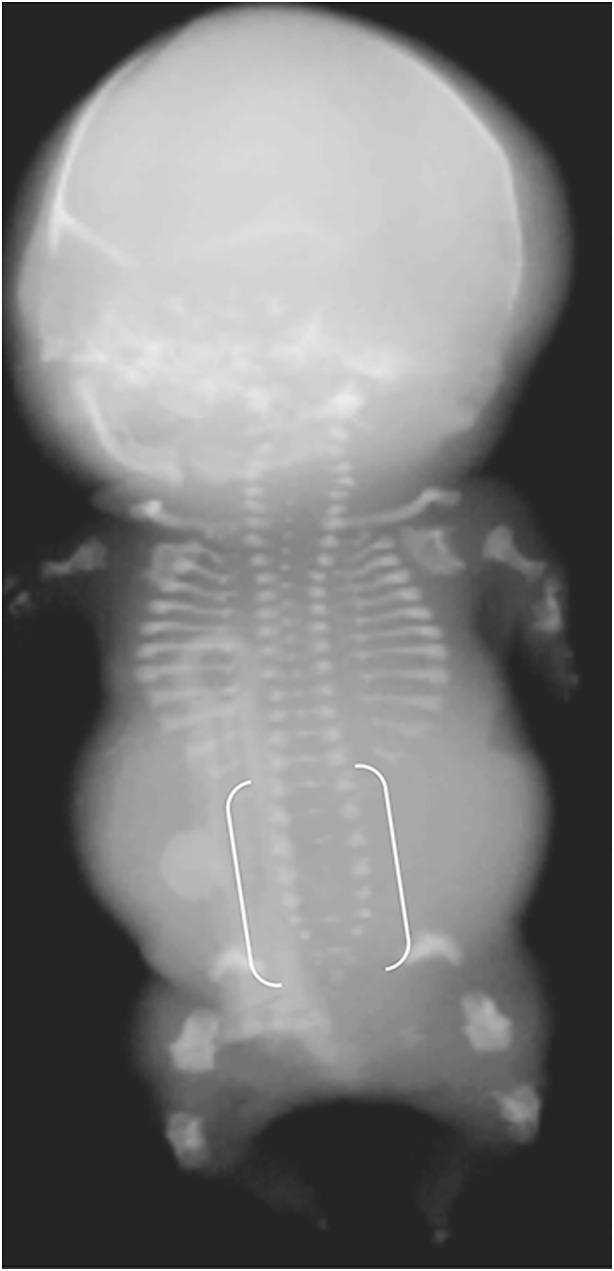

Perinatal hypophosphatasia (HPP) is a rare, potentially life-threatening, inherited, systemic metabolic bone disease that can be difficult to recognize in utero and postnatally. Diagnosis is challenging because of the large number of skeletal dysplasias with overlapping clinical features. This review focuses on the role of fetal and neonatal imaging modalities in the differential diagnosis of perinatal HPP from other skeletal dysplasias (e.g., osteogenesis imperfecta, campomelic dysplasia, achondrogenesis subtypes, hypochondrogenesis, cleidocranial dysplasia). Perinatal HPP is associated with a broad spectrum of imaging findings that are characteristic of but do not occur in all cases of HPP and are not unique to HPP, such as shortening, bowing and angulation of the long bones, and slender, poorly ossified ribs and metaphyseal lucencies. Conversely, absent ossification of whole bones is characteristic of severe lethal HPP and is associated with very few other conditions. Certain features may help distinguish HPP from other skeletal dysplasias, such as sites of angulation of long bones, patterns of hypomineralization, and metaphyseal characteristics. In utero recognition of HPP allows for the assembly and preparation of a multidisciplinary care team before delivery and provides additional time to devise treatment strategies.

围生期低磷酸酯酶症(HPP)是一种罕见的、可能危及生命的遗传性全身性代谢性骨病,在子宫内和出生后都可能难以识别。由于大量骨骼发育异常具有重叠的临床特征,诊断具有挑战性。本综述重点关注胎儿和新生儿成像模式在围生期HPP与其他骨骼发育异常(如成骨不全、弯肢侏儒症、软骨发育不全亚型、低软骨发育不全、锁骨颅骨发育不全)的鉴别诊断中的作用。围生期HPP与一系列广泛的影像学表现相关,这些表现是HPP的特征性表现,但并非在所有HPP病例中都出现,也不是HPP所特有的,如长骨缩短、弯曲和成角,以及肋骨纤细、骨化不良和干骺端透亮区。相反,全骨无骨化是严重致死性HPP的特征,且与极少数其他病症相关。某些特征可能有助于将HPP与其他骨骼发育异常区分开来,如长骨成角部位、矿化不足模式和干骺端特征。在子宫内识别HPP可在分娩前组建和准备多学科护理团队,并为制定治疗策略提供更多时间。